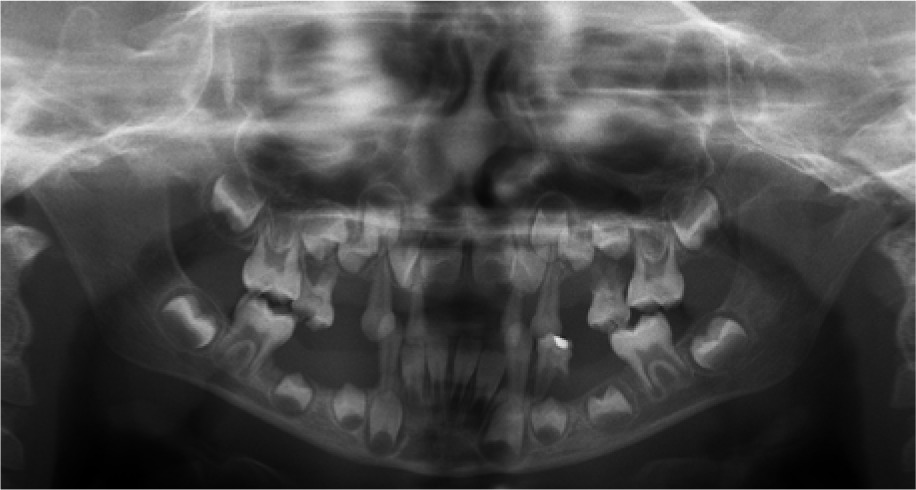

When the patient was 10, the exposure of two-thirds of palatal roots and third-degree loosening of teeth were observed (Fig. 3). A panoramic radiograph picture was taken (Fig. 4), which revealed complete absence of the bone base in all permanent first molars. Teeth 16 and 26 were qualified for extraction, which was performed in an outpatient setting under local anesthesia and antibiotic treatment (clindamycin, 10 mg/kg/dose). The obtained material from granulomatous lesions was submitted for histopathological examination, the results of which indicated non-specific inflammatory granulation tissue.